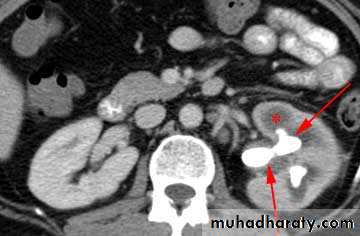

WHAT IS THE MOST APPROPRIATE RADIOLOGICAL MODALITY ?

CT scanWHAT IS THE DIAGNOSIS & THE CAUSATIVE ORGANISM ?

Struvite stone ( MAP stone ).Urea splitting microorganisms.